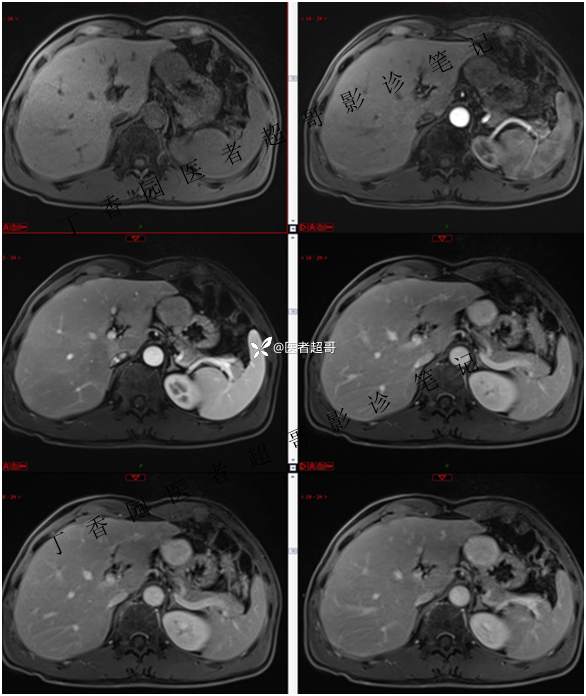

肝胃间隙肿瘤,间质瘤?平滑肌瘤?还是鞘瘤?有结果,请分析!

主 诉:查体发现肝占位3天。

现病史:患者于3天前查体行肝胆脾胰肾彩超示肝内实性占位,无恶心、呕吐,无发热、寒战,无腹胀、腹泻,进一步于医院行上腹部CT增强示:肝胃交界处肿块。未行特殊治疗。今患者为求进一步治疗,来我院就诊,门诊以“肝占位性病变”收入院。患者自发病以来,神志清,精神可,饮食睡眠可,二便可,体重近期未见明显变化。